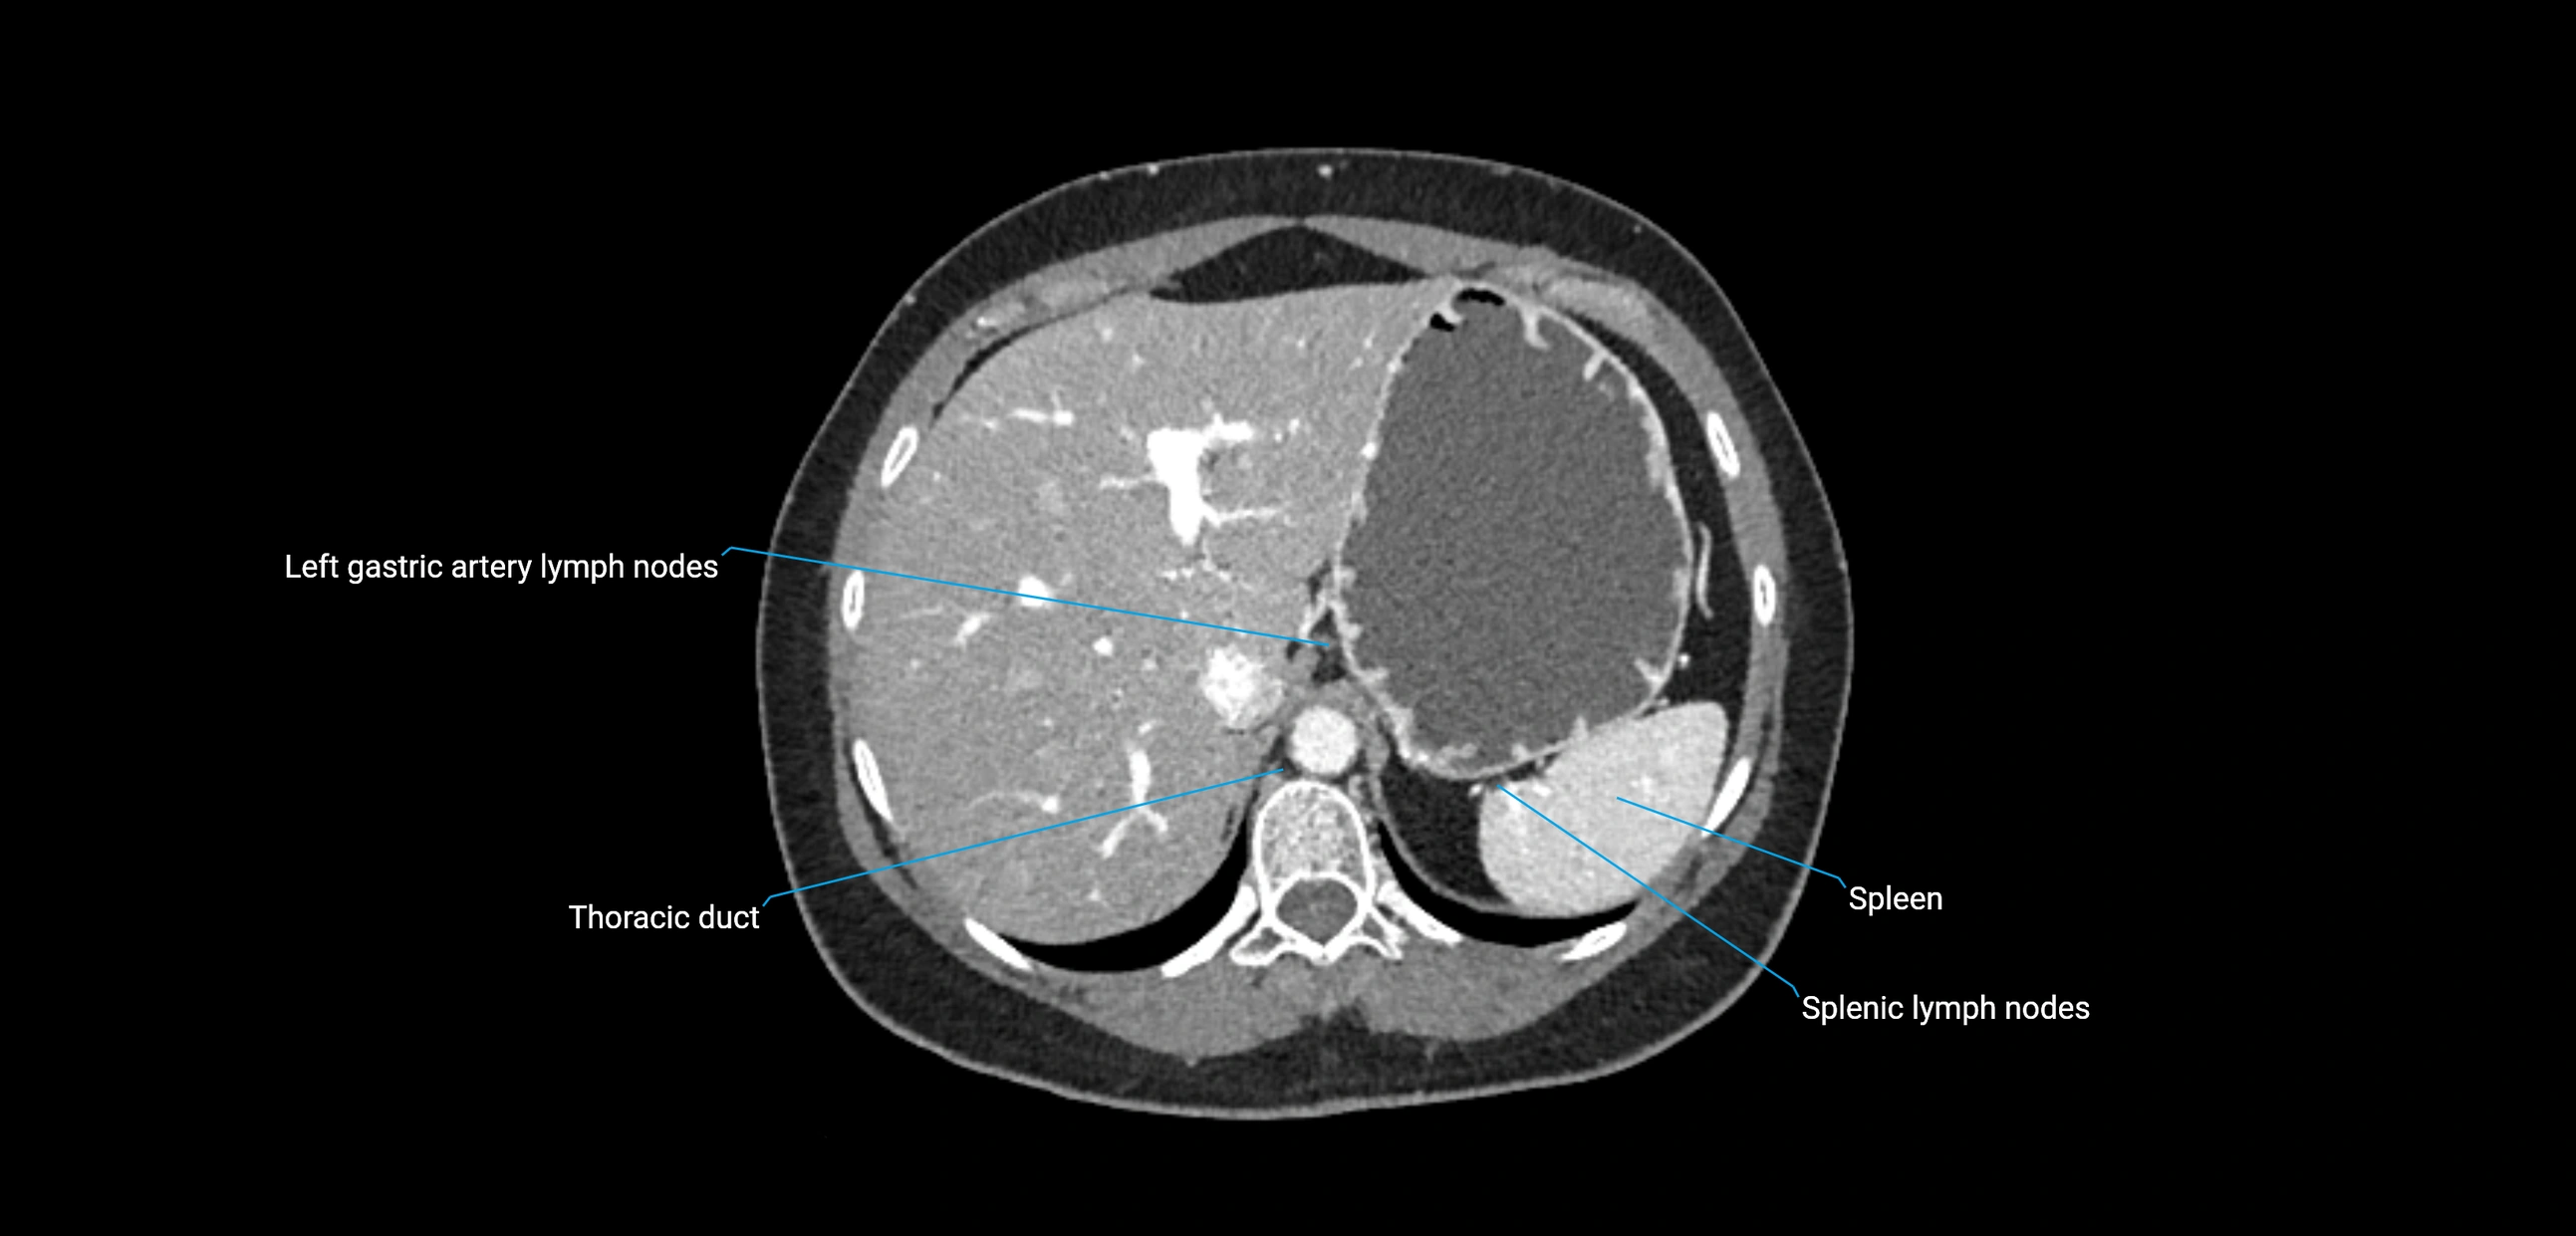

CT image

image